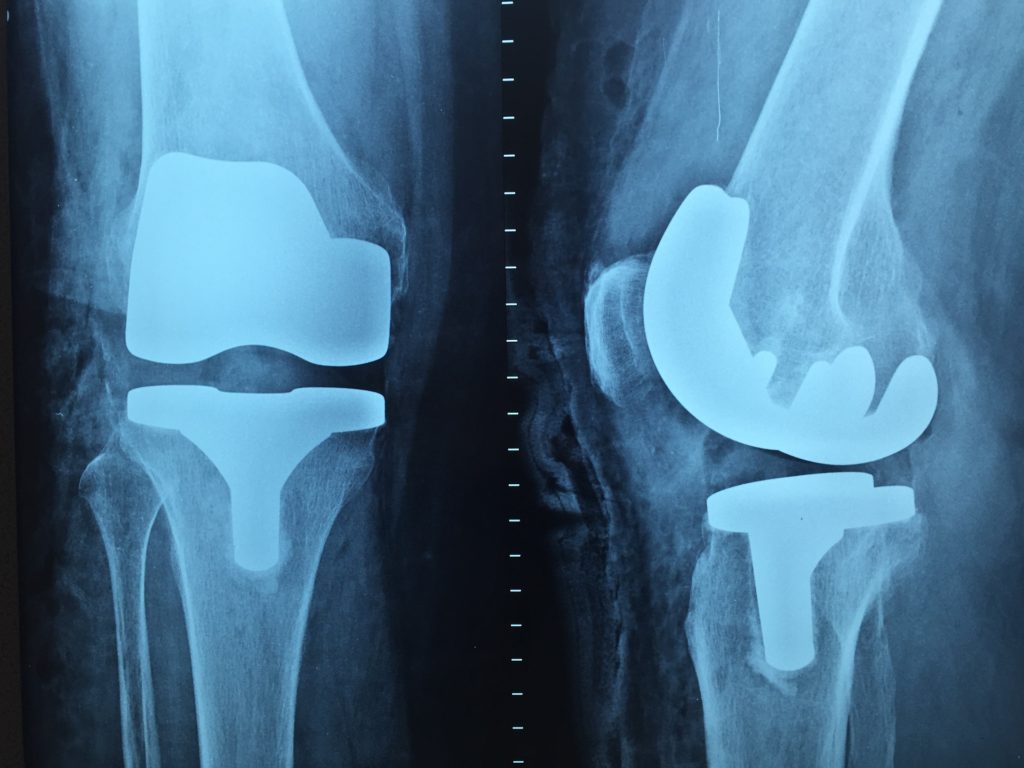

Laman web rasmi mempunyai halaman berasingan untuk ortopedik untuk orang dewasa, menunjukkan kakitangan perubatan klinik dan senarai perkhidmatan yang disediakan, termasuk penggantian sendi, pembedahan memelihara organ, dan pembedahan arthroscopic.

Pakar menjalankan operasi berikut:

Doktor jabatan mempunyai pengalaman yang luas dalam operasi berteknologi tinggi pada bahagian bawah dan atas menggunakan osteosintesis intramedullary dan tulang yang tersumbat.